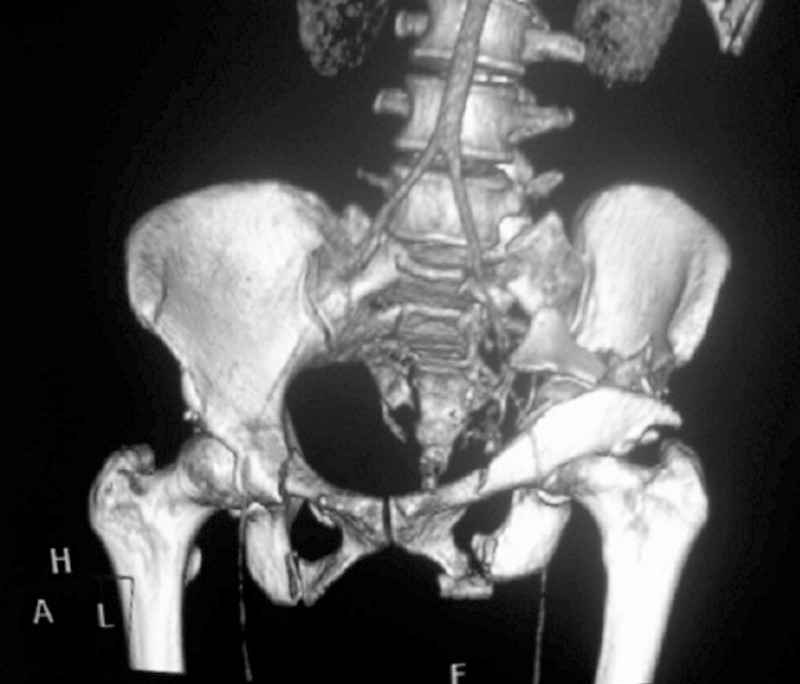

I'm posting this case on behalf of Dr. Pedro Caba, he is unable to post but able to read. 41 yo female , fall from 10 meters five days ago. Hemodynamically unstable on admission treated by angio and embolization and skeletal traction, with no external support. No associated injuries. Based on CT scan the pt has a both column fracture with conminuted dome and displaced anterior column and a sacral Denis 1 fracture with a displaced left ala. I think the best approach for the acetabular fracture is ilioinguinal with Smith-Petersen extension but don't know exactly the sequence . Will you start with the sacral fracture? Which technique? Thanks in advance Pedro Caba Unidad de Trauma Hospital 12 de Octubre Madrid Spain

This complex and displaced sacral injury is likely an H pattern...2 hemipelvic components, an upper sacral component which remains attached to the lumbar spine, and a caudal sacral component...there are typically anterior ring injuries as well...in this patient's example, the left sided acetabulum also has been exploded.

Most H pattern sacral fractures have the transverse fracture limb of the "H" at the upper-second sacral segment junction or disc region...some fracture thru the second segment, and some or at other sites...but most yield thru the upper-second sacral segments junction...with variable traumatic associated neurological findings.

The hemipelvic components' displacements depend on their instability...this patient's left side seems to be the worst.

The transverse fracture limb liberates the upper sacral segment and its attached lumbar-thoracic-cervical spine to displace...usually anteriorly and in kyphosis.

The kyphosis and anterior translation of the upper sacral segment distorts the safe area for iliosacral screw usage...the imaging allows the surgeon to preoperatively plan if iliosacral screw fixation is a safe possibility.

For this patient (according to the limited imaging available), it would seem that a combination of lumbo-pelvic fixation along with transiliac transsacral fixation is optimal...BUT the left sided pelvic implants must be applied in consideration of and in anticipation of the necessary acetabular fixation implants.

So you are correct, this pattern likely needs a great reduction and a powerful fixation construct to be durable...but the operative exposure and implants must be planned carefully if the acetabular fracture is to be accurately reduced and well stabilized.